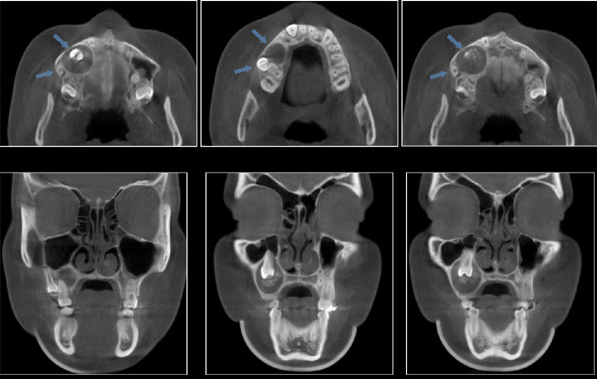

Paciente femenino 14 años de edad,asintomática. Es referida a la consulta para la evaluación radiográfica por persistencia de las piezas 5.5 y 5.4 . A la evaluación intraoral se observa aumento de volumen a nivel apical de las piezas 1.6 , 5.5 y 5.4 de consistencia dura no dolorosa a la palpación, la mucosa que lo recubre se presenta de características normales. Se le realiza el estudio con tomografía volumétrica (Picasso E-WOO),se grafican cortes panorámico, transaxiales, sagital, coronales y axiales, los que muestran una imagen mixta asociada a la retención de la pieza 1.4, que condiciona el desplazamiento hacia distal de la pieza 1.5 que se encuentra próxima a la tabla ósea vestibular y a nivel apical de la pieza 1.6; así mismo apreciamos el desplazamiento hacia mesial de la pieza 1.3, como también la expansión de las tablas óseas vestibular y palatina. Obsérvese la presencia de imágenes hiperdensas alrededor de la corona de la pieza dentaria, compatibles con calcificaciones en el interior de la lesión.